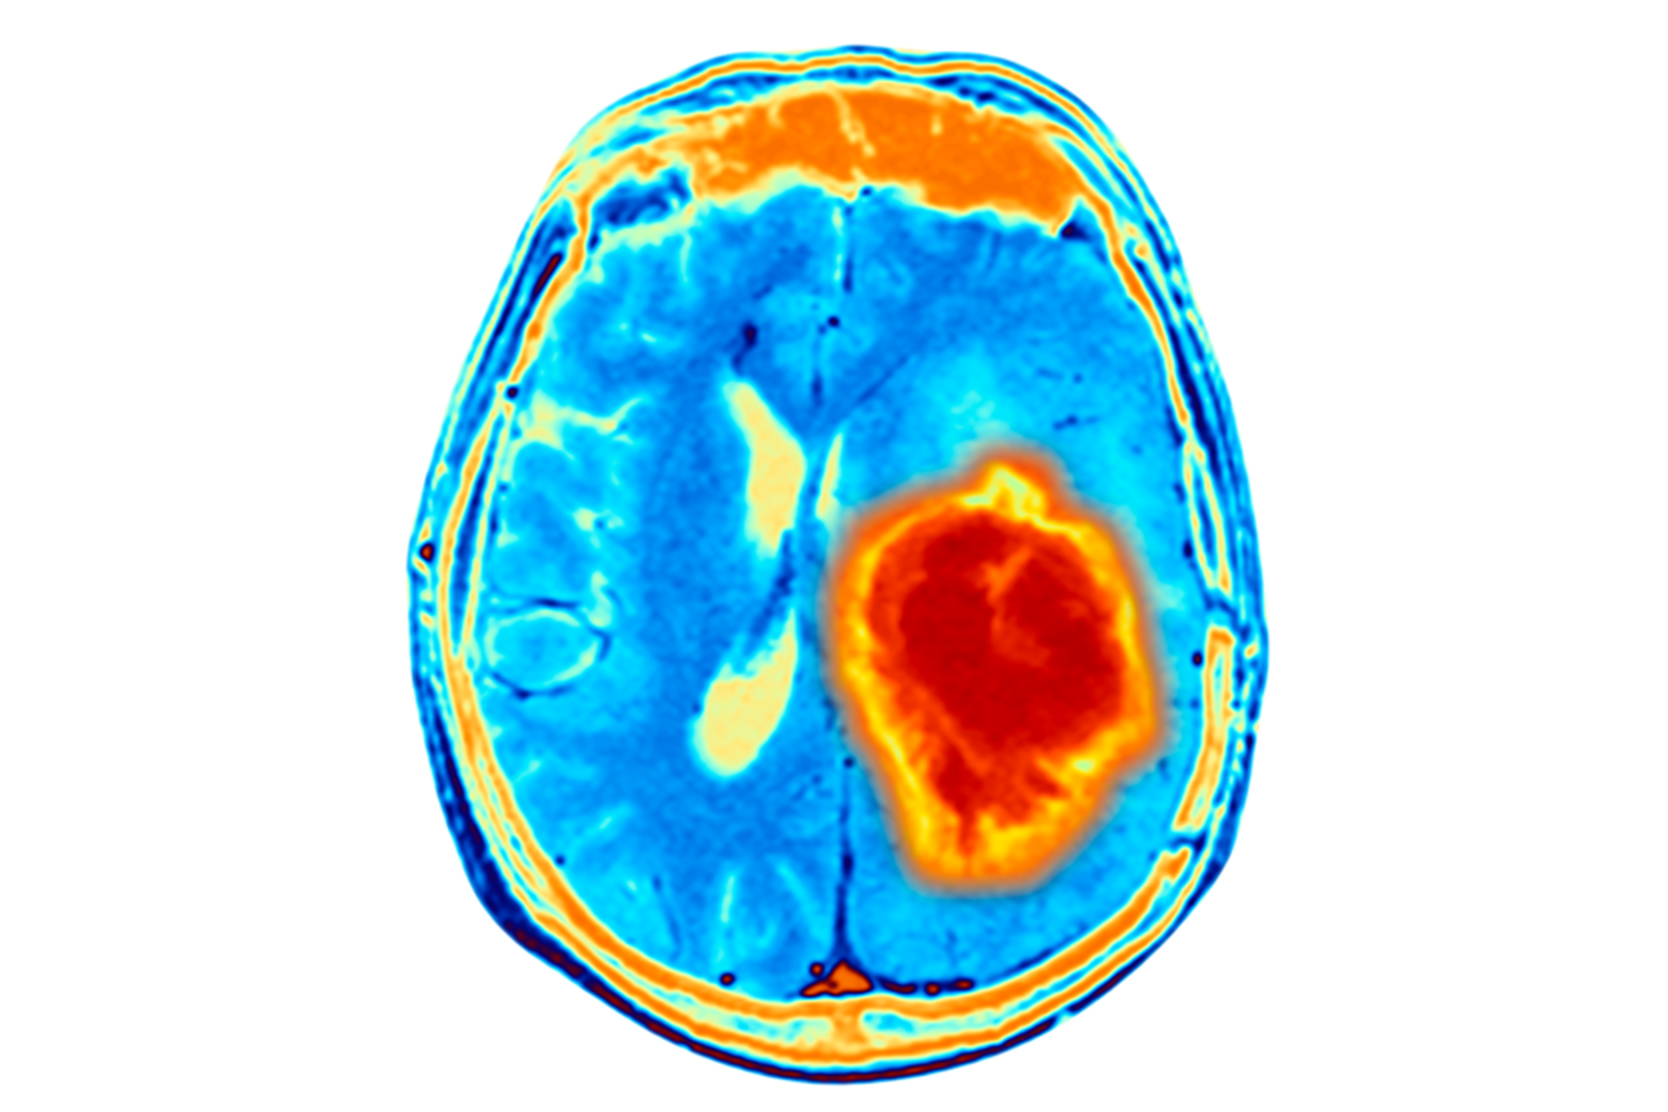

Brain tumor protocol

Patients with high-grade brain tumors – in particular those under age 3 and those whose cancer progresses after standard chemotherapy and radiation – may be candidates for intensive chemotherapy and autologous BMT. The decision is based on the individual child's circumstances, in consultation with the pediatric neuro-oncology team.